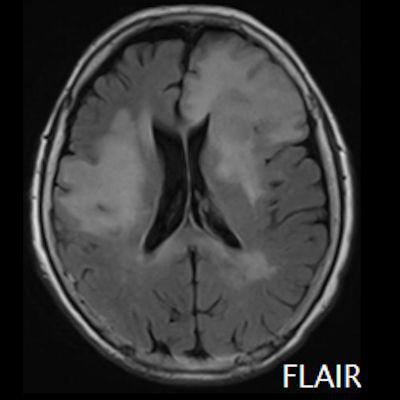

- (A) Her iki periventriküler beyaz cevherde aksiyel T2A, FLAIR serilerde hiperintens, T1A hipointens geniş ödem alanları (oklar) izlenmektedir. Sol frontalde T2A’da hipointens kitle lezyonuna (ok) dikkat ediniz.

- Genellikle supratentoriyal alanda, bazal ganglion, periventriküler beyaz cevher, orta hat ve korpus kallozum vb. yerleşme eğiliminde tek veya multipl kitleler şeklinde görülür.

- Kitleler çoğunlukla solid ve homojendir.

- MRG’de, lenfomalar tipik olarak T2A sekanslarda hipointens olup DAG’de belirgin difüzyon kısıtlanması gösterirler.